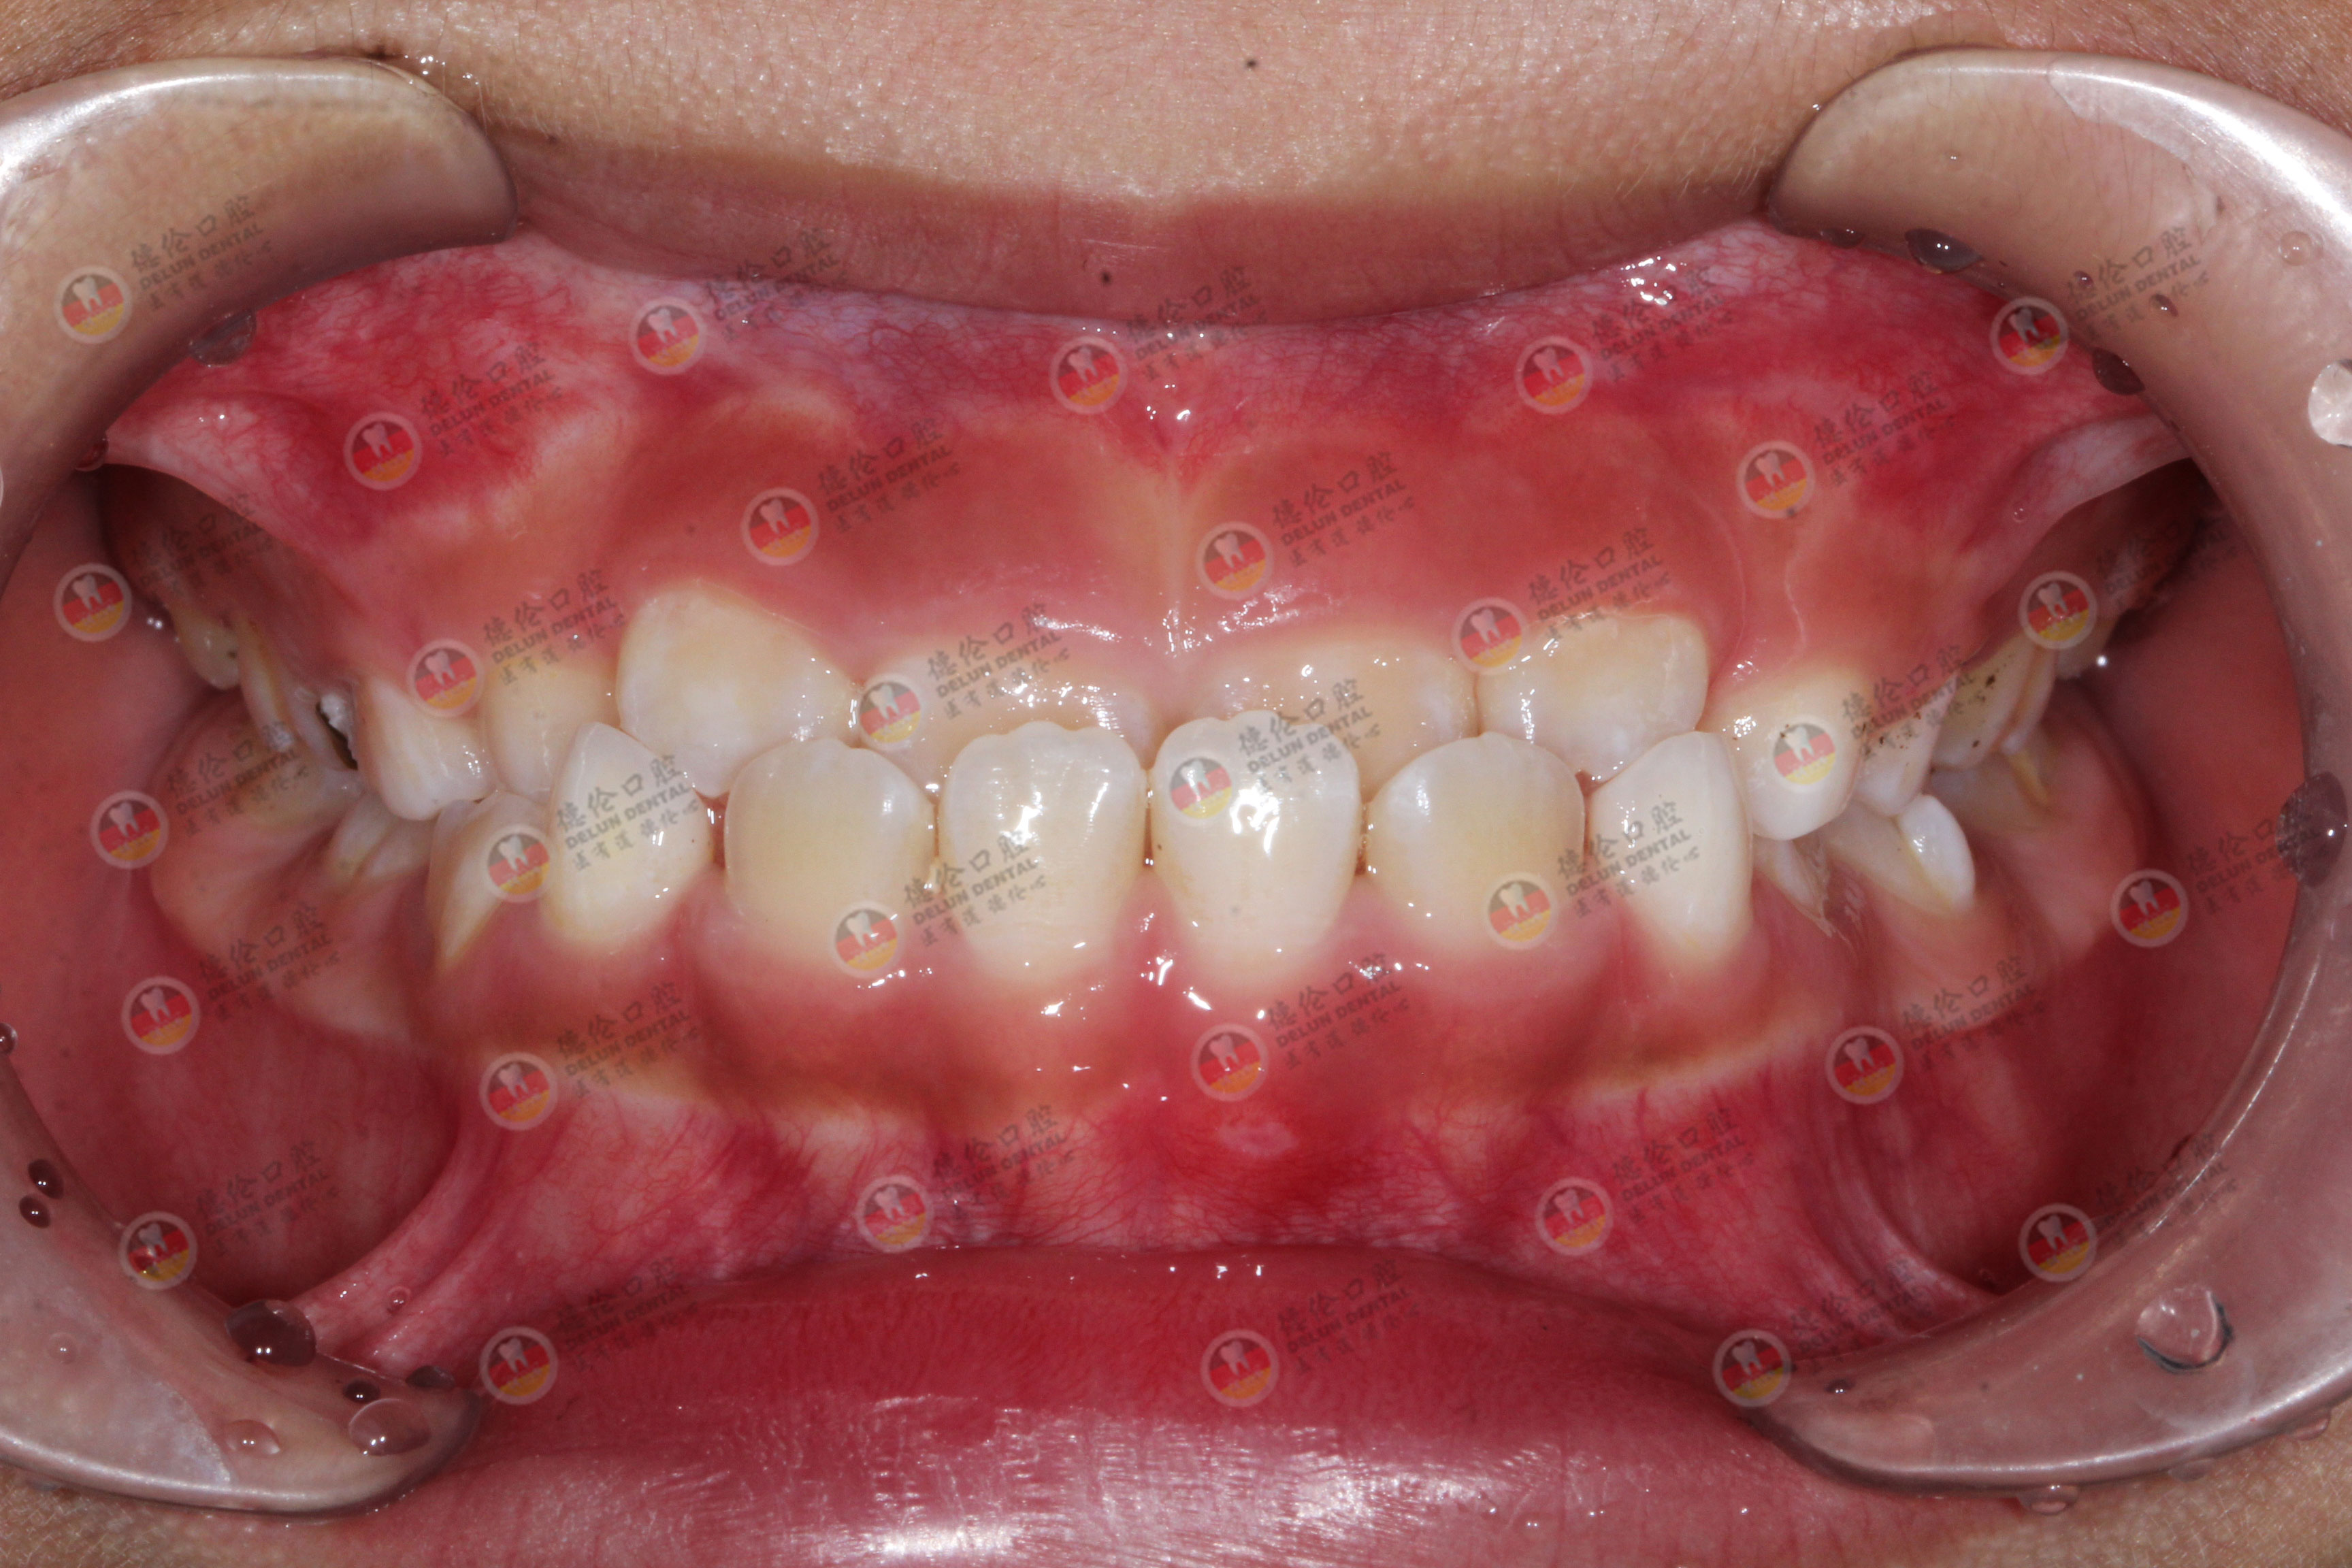

目前,错颌畸形有 5 种常见形态,每种在面部表现上各有差别,对颜值的影响也不大一样,可以对镜自查,你是否也存在这类问题?

常见牙齿畸形

1.反颌

也就是俗称的「地包天」,下排牙齿包住一部分上牙,导致咬合不齐、下巴立体度不够,对面型造成影响,侧面看上去像“月牙脸”。

2.牙齿前突

即常见的「龅牙」,主要表现为上下牙齿向前延伸,严重的可能会引起闭唇困难,影响唇形、侧面脸型,加深法令纹。

3.牙齿拥挤

简单理解,如果把整排牙齿看做军训时规整的队列,有几个「调皮捣蛋」的牙齿跑出了队伍,导致前后参差不齐。主要影响咬合,口腔清洁不便,也不太美观。

4.深覆颌

一种上下牙垂直关系异常的表现,简单来说就是「上牙过度包住了下牙」或「完全看不到下牙」,往往会出现露龈笑、笑容僵硬以及下巴后缩等情况,也就是大家常说的“小下巴”。

5.开颌

顾名思义,指上下牙之间存在较大的间隙,难以正常咬合和咀嚼。通常与不良习惯有关,如吮指、口呼吸、吐舌、舔牙等,可能导致说话漏风,嘴巴无法紧闭,面部不协调。

以上只是一些较为常见的错颌症状,除了影响牙齿整齐外,更会导致咬合不协调,若是刷牙不彻底,易发生龋齿等牙病。